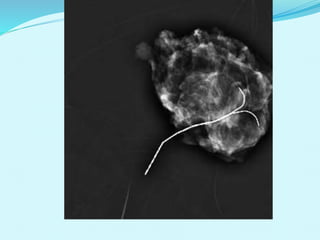

BIOPSIA TUMORES NO PALPABLES

Se descubren con técnicas

de imagen.

Inyección medio de

contraste y tinta o índigo

carmín

Aplicación de arpón.

Tener coordenadas de

BIOPSIA POR MARCAJE

INDICACIONES

 Lesión no palpable

 Microcalcificaciones

CONTRAINDICACIONES

 Tumor palpable

 Lesiones benignas

 Sin cambios en Mastografías